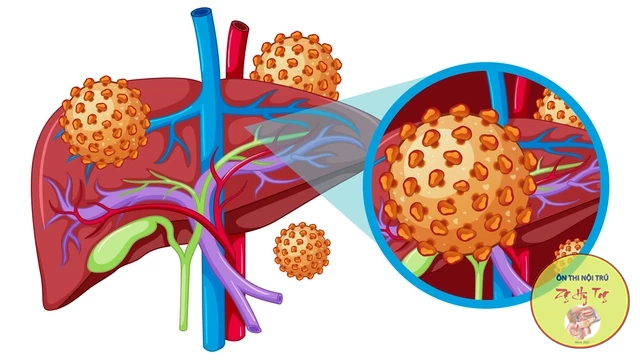

Ca lâm sàng thực tế, vận dụng lý thuyết bệnh học